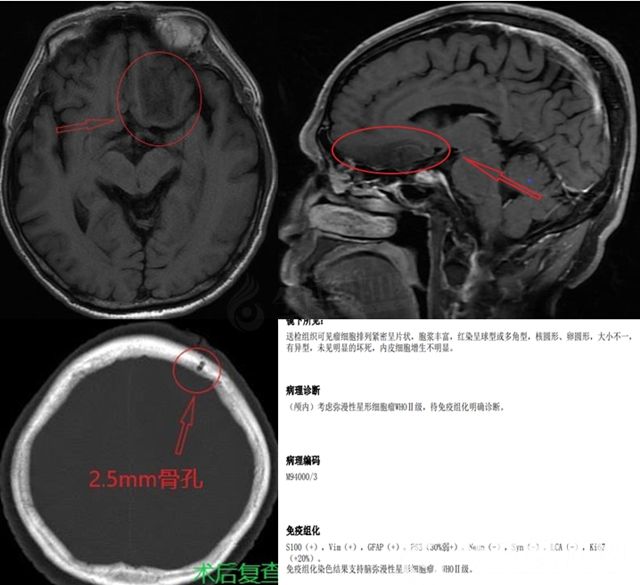

病例一:患者李某,5年前無誘因間斷出現(xiàn)意識不清,近2年出現(xiàn)記憶力下降。經(jīng)頭部CT及核磁等影像學(xué)檢查發(fā)現(xiàn),顱內(nèi)占位但難以確認(rèn)病變性質(zhì)。入院后,經(jīng)神經(jīng)外二科醫(yī)療團(tuán)隊討論,決定實施機(jī)器人手術(shù)確定病理性質(zhì)和診療方案,并于全麻下實施了機(jī)器人輔助腦穿刺活檢術(shù),手術(shù)于20分鐘內(nèi)完成,過程順利,患者術(shù)后迅速蘇醒。術(shù)后患者狀態(tài)同術(shù)前相比,無任何不良反應(yīng)。最終,明確病理診斷為膠質(zhì)瘤II級,患者接受了開顱手術(shù)治療。